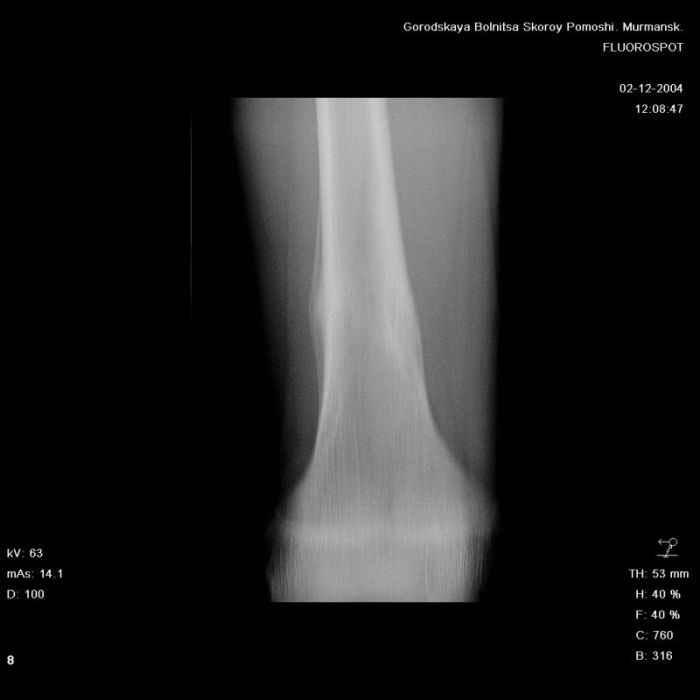

Анамнез практически никакой: в следствие травмы (растяжение связок коленного сустава) от 07.11.2004 выполнены Rg-граммы в травмпункте и обнаружено опухолевидное образование. Первичные Rg-граммы я не публикую, так как они заметно худшего качества, да и динамики за прошедшие три недели не отражают. Болевой синдром купирован в течение трёх дней. В настоящий момент мальчика ничего не беспокоит. Ходьба не нарушена, опухоль пальпируется с трудом по задней поверхности в н\3 правого бедра, пальпация безболезненна, объем движений в суставах правой нижней конечности полный и симметричный. Кожа над опухолью не изменена. В нашей клинике проведено дополнительное обследование: общие анализы крови и мочи, биохимия крови без особенностей. Выполнены Rg-граммы на цифровом Siemens обычные и продольные томограммы срезами 3-5 мм, а также компьютерная томография поперечными срезами по 5 мм. Прошу обратить внимание, что на приведённых томограммах видны две полости 10х15 мм и 15х60 мм. Также имеются два опухолевидных образований наслаивающихся друг на друга: уплощённое и вытянутое 10х100 мм и элипсовидной формы 15х30 мм. Это хорошо заметно на фото a_1.jpg c_1.jpg и d_1.jpg. Плотность внутри полостей 125% от плотности костномозгового канала, плотность наружного опухолевидного образования 55% от плотности кортикального слоя. Также отмечается линия перелома по центру наружного опухолевидного образования. Исходя из полученных данных мнения в плане диагноза несколько разделились от 1)сочетания кортикальной фиброзной дисплазии и латентно протекавшего маршевого перелома н\3 правого бедра до 2)остеосаркомы. В отношении первого варианта не сходится отсутствие клиники при переломе такой крупной кости как бедро, второй вариант вообще оставлю без комментария, ибо некомпетентен. Хотелось бы услышать мнения коллег, с удовольствием ознакомлюсь с любыми предположениями и замечаниями. С уважением, Александр Е. Клоков Отделение детской ортопедии и травматологии БСМП г. Мурманска.